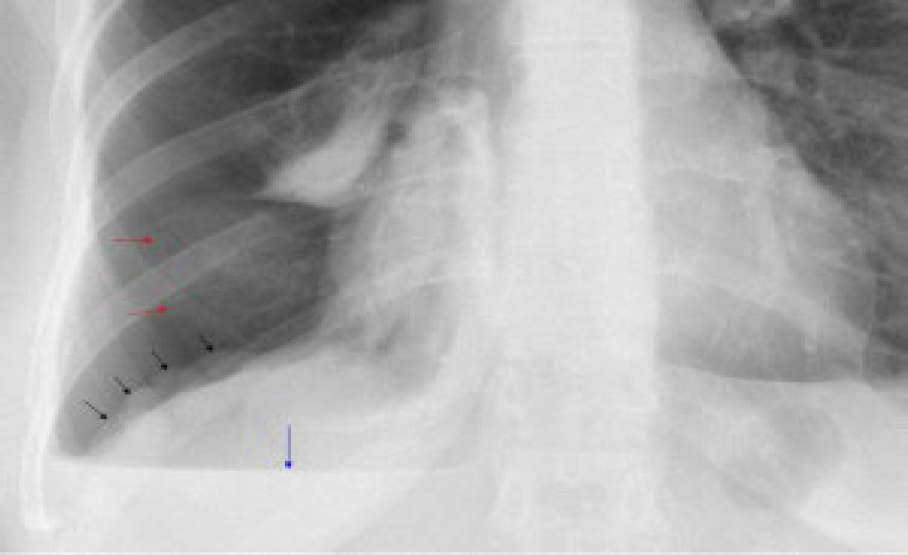

臨床診斷為主,當生育年齡女性有反覆胸痛、氣胸,且與月經週期相關時需高度懷疑。實驗室檢查可能可以發現CA-125上升,但不具有特異性。影像上,胸腔X光可能可以看到橫膈膜上多個小結節(圖三黑色箭頭),其來源是子宮內膜異位造成橫膈膜孔洞,同時肝臟往胸腔突出所造成,在胸腔電腦斷層也可以看到相同特徵(圖四)。對於橫膈膜上的子宮內膜異位,核磁共振有較前兩者高的敏感性及特異性,其在fat-suppressed T1-weighted MRI可以看到訊號增強的病灶(圖五)。最後則是手術的方式,如胸腔鏡手術( video-assisted thoracoscopy, VATS ),直接看到病灶(圖六:橫膈膜結節,圖七:橫膈膜上的子宮內膜),其病理檢驗可看到子宮內膜的間質細胞及腺體。

圖三胸腔X光可能可以看到橫膈膜上多個小結節(圖三黑色箭頭)

(圖片來源: Catamenial pneumothorax. J Thorac Dis. 2014;6(S4):S448-S460. )